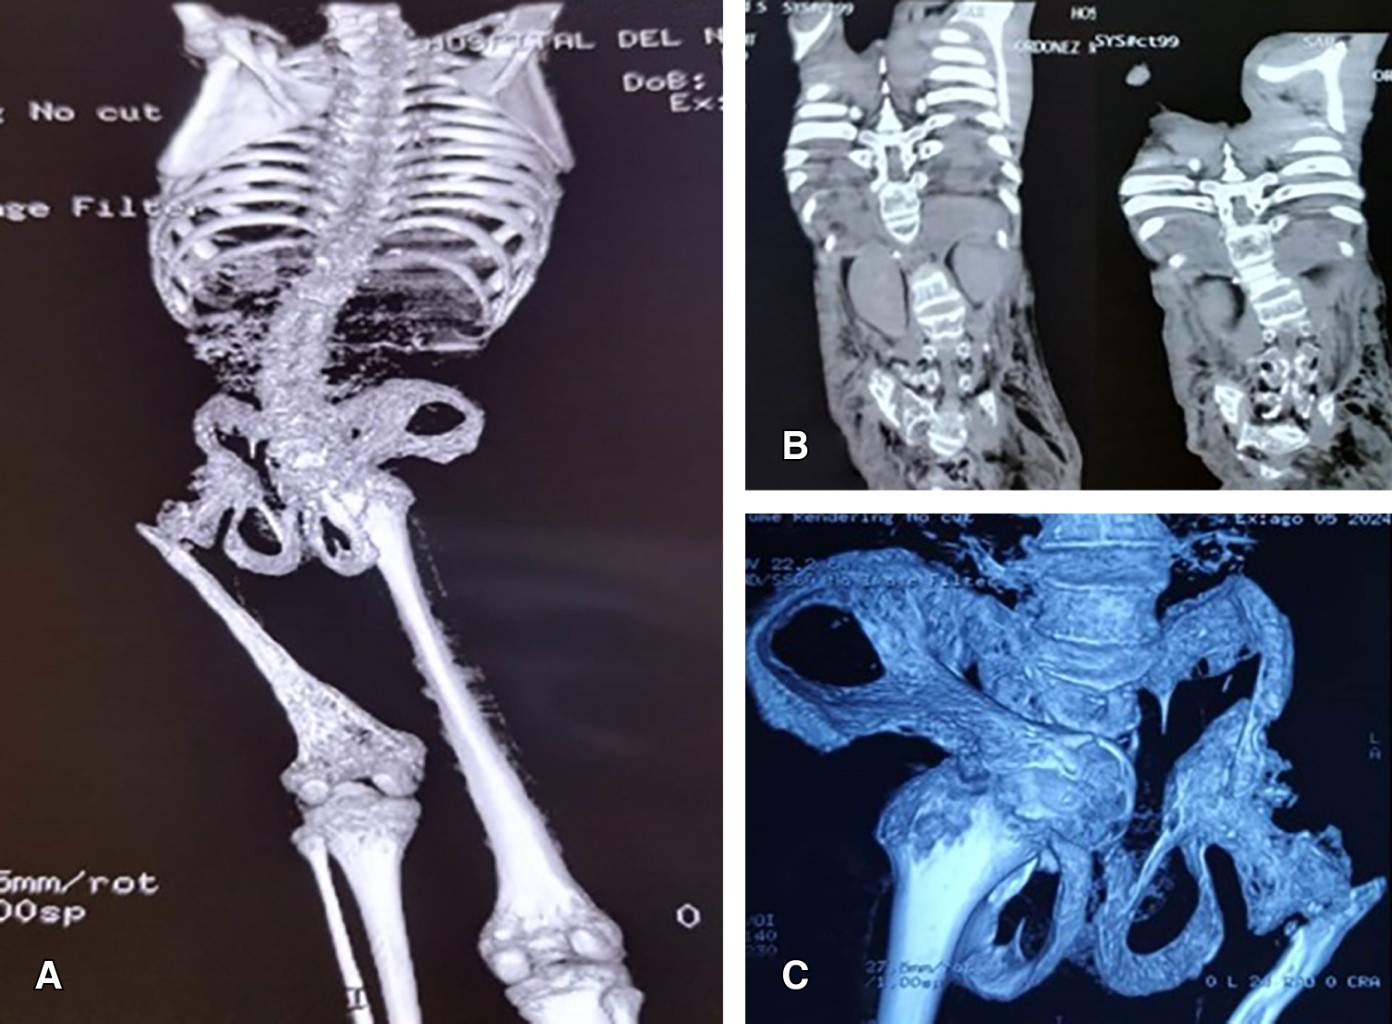

Tras mes y medio de hospitalización y 20 días de manejo antimicrobiano se decide cierre de conducto linfático por parte del servicio de cirugía, que si bien durante los primeros días muestra decremento del derrame pleural, ésta recidiva nuevamente con gasto alto. Durante su seguimiento por parte del servicio de ortopedia pediátrica tras la documentación del quilotórax masivo y la evanescencia progresiva de las regiones óseas de la columna dorso lumbar, pelvis y caderas se decide la toma de biopsia de tejido óseo de región clavicular (Figura 2). Esto con el objetivo de llegar al diagnóstico, ya que nos encontrábamos ante la alta sospecha de un síndrome de angiogénesis y linfangiomatosis. Cabe destacar que la sospecha diagnóstica se consideró ya que se contaba con el conocimiento previo de la existencia de este padecimiento. El resultado histopatológico de la muestra ósea reportó: angiomatosis y linfangiomatosis compatible con síndrome de Gorham-Stout (Figura 3).

Se inicia sirolimus 1.6 mg al día y se continúa con octreótida, mostrando una reducción del quilotórax a 90 mL, una mejoría hemodinámica y ventilatoria. Actualmente el paciente, tras un año de evolución, se encuentra hemodinámicamente estable, sin recidiva pulmonar. Sin embargo, a nivel osteomuscular con un pronóstico desfavorable, se observa un fenotipo caquéxico, con tórax en tonel y atrofia muscular (Figura 4). Topográficamente persiste la destrucción ósea marcada a nivel columna, pelvis y cadera izquierda.

Figura 2